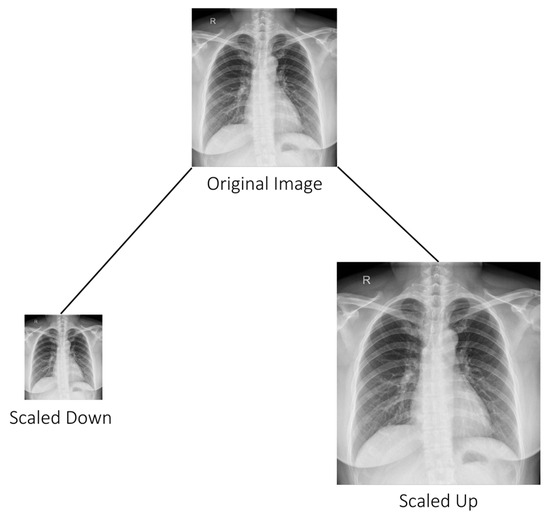

Scaling is another image augmentation technique that involves resizing images to different resolutions as shown in Figure 7. This process can be performed by either increasing or decreasing the image size while preserving the aspect ratio, which helps to prevent distortion [50].

Figure 7. Showing scaled images [51].